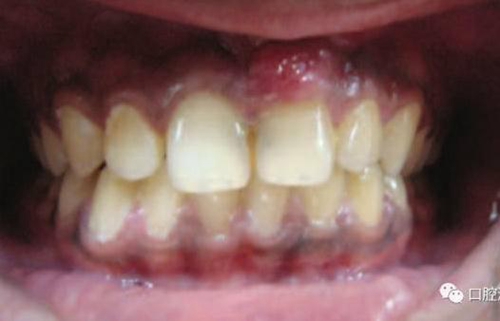

11、21 治療前

對(duì)瘺管位置進(jìn)行激光氣化